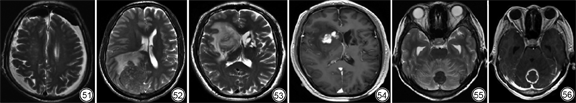

颅内积气常见于外伤、手术及感染。气体可积聚于脑实质、蛛网膜下腔、脑室、硬膜内外等,在各序列上均呈极低信号(图51)。